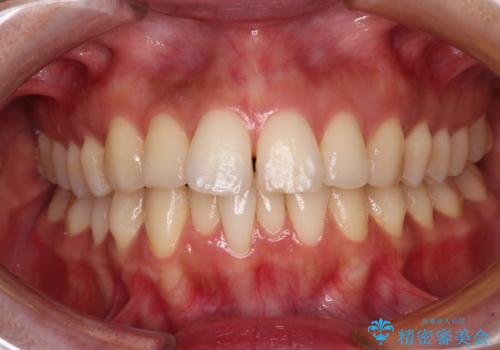

【モニター】飛び出した上顎前歯を抜歯矯正で引っ込める ワイヤー装置の抜歯矯正治療

- 口元の閉じにくさを気にして来院された患者様です。

上下ともに歯列が前方に突出していたため、上下左右の第一小臼歯4本を抜去し、ワイヤー装置による矯正治療を行うこととしました。

舌の突出癖による影響もあったため、舌のトレーニングを並行して実施しました。

舌の突出癖がなかなか改善されず、上下前歯の接触がやや甘い状態での仕上がりとなりました。

接触が甘い場合、上顎前歯の叢生が後戻りを起こしやすくなるため、治療終了後の保定期間でも舌のトレーニングを継続するように指示しています。